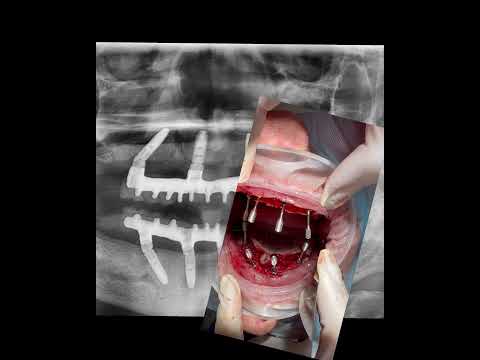

All on 4 на верхнюю челюсть. Время операции 2.5 часа и у пациента новые зубы. Имплантация зубов.Скачать

Имплантация all on 4 ( все на 4х имплантах)Скачать

Фиксация верхней челюсти на All on 4. Имплантация зубов.Скачать

All on 4 / All on four - протезирование всех зубов на 4 имплантах за 1 день с постоянным протезомСкачать